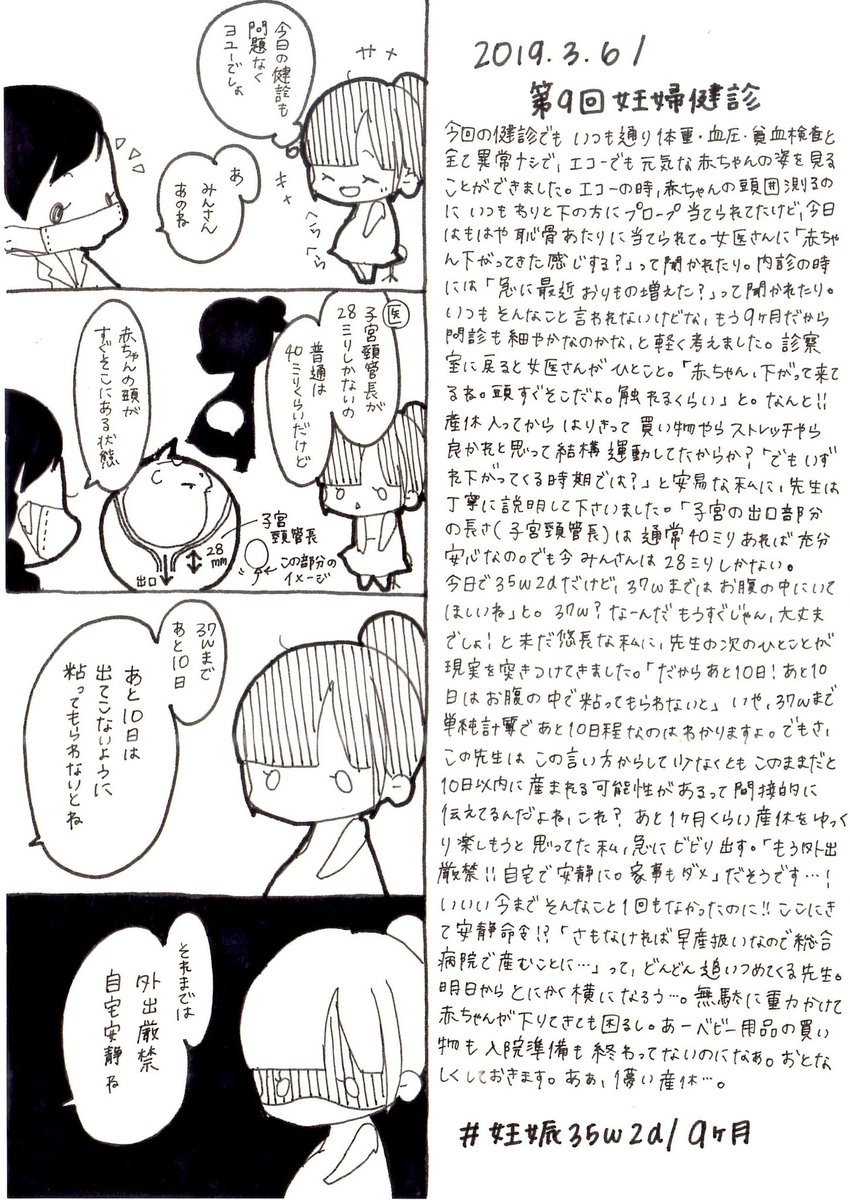

2019.3.6 ここまで順調に進んできた妊娠生活。 今回の妊婦健診にて、まさかの診断が… エコー載せます、閲覧注意! #育児漫画 #育児日記 #妊娠 #妊娠後期 #妊娠9ヶ月 #妊婦健診 #エコー #子宮頸管長 #切迫早産 #ママ垢さんと繋がりたい #オリジナル漫画 #絵描きさんと繫がりたい pic.twitter.com/1jipVynvU2